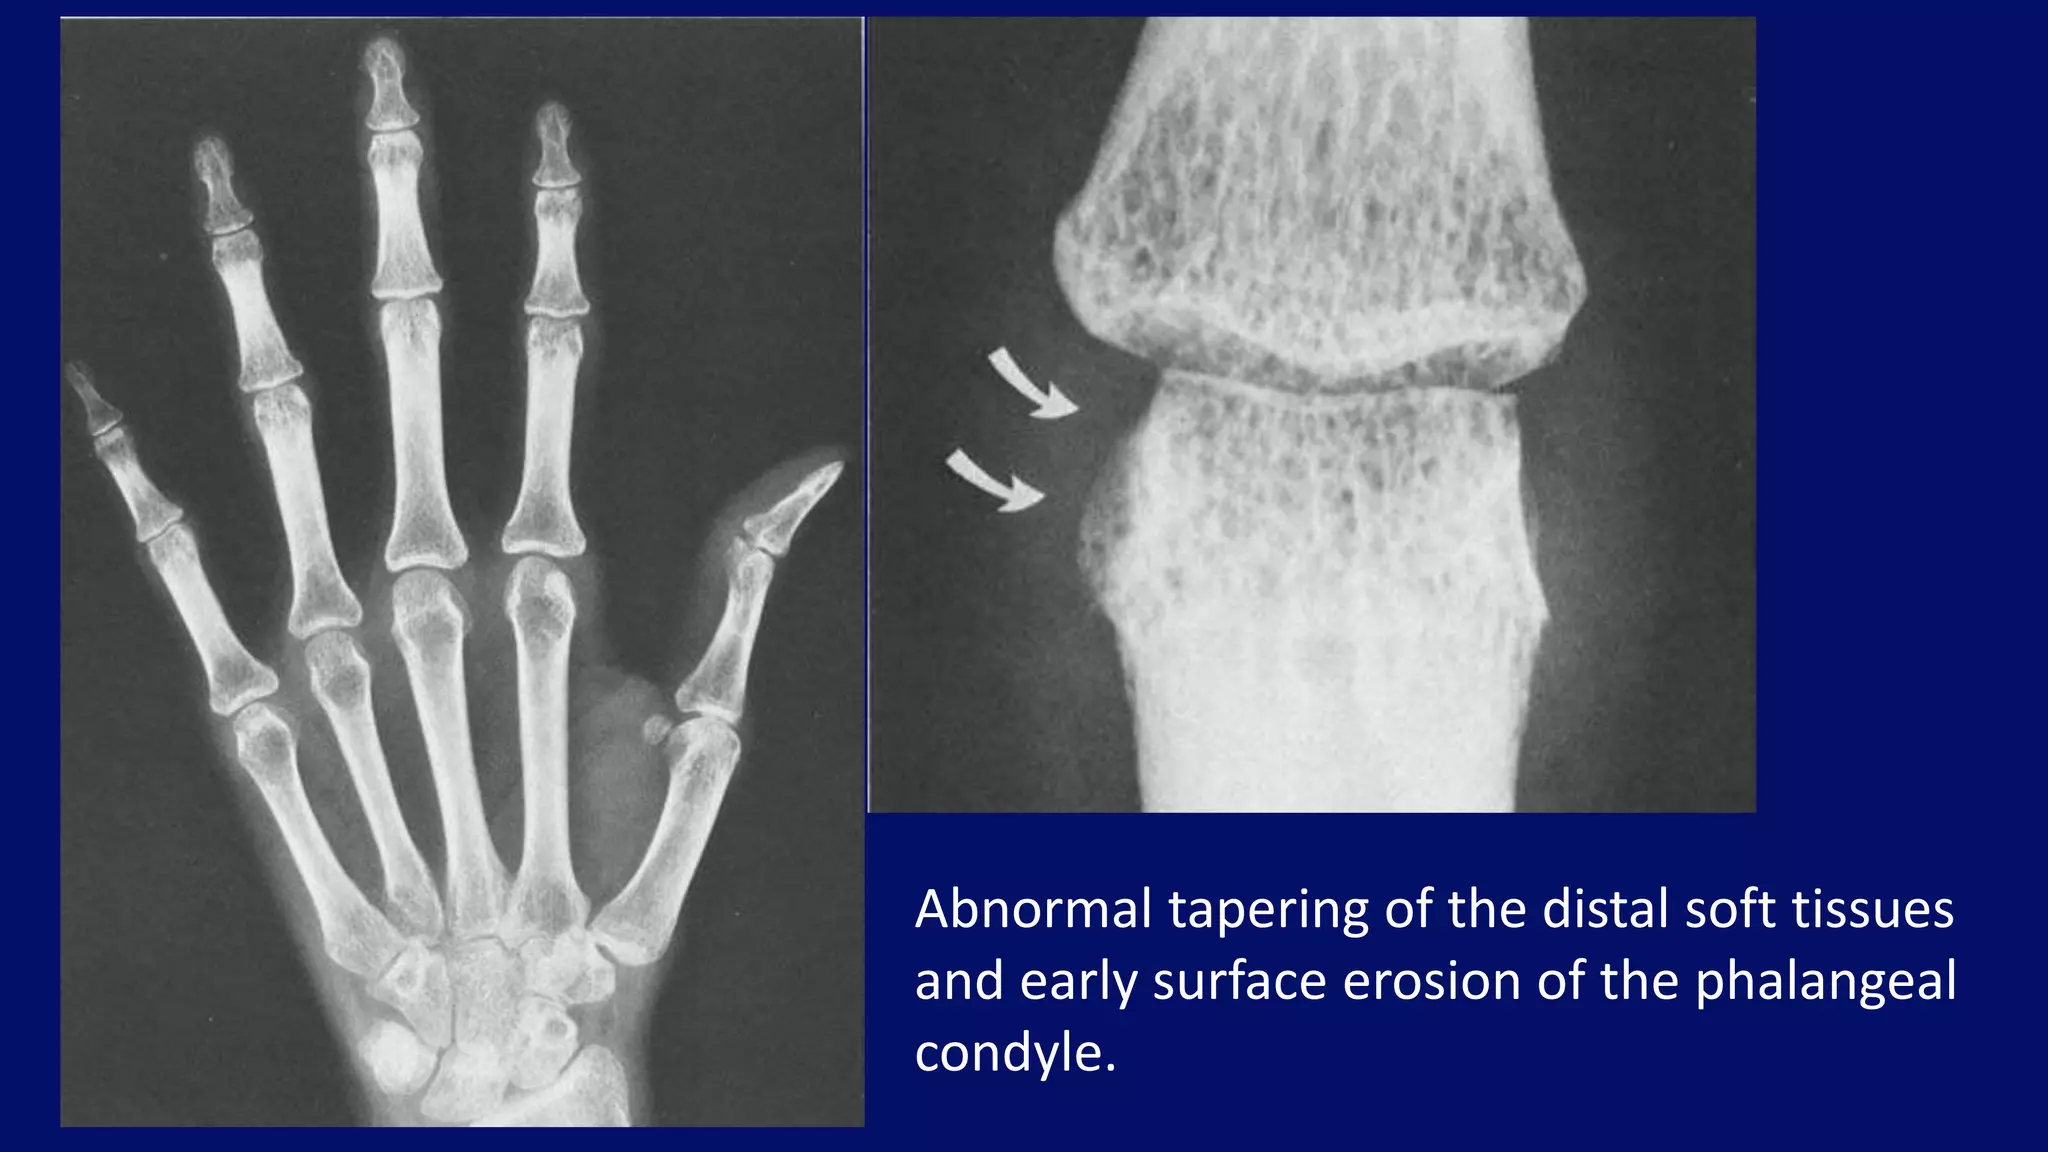

Abnormal tapering of the distal soft tissues

and early surface erosion of the phalangeal

condyle.

• #86 Moderate juxta-articular demineralization associated with periarticular soft-tissue swelling and abnormal tapering of the distal soft tissues (A). Close-up view of proximal interphalangeal joint of this patient (8) demonstrates capsular distension and early surface erosion of the phalangeal condyle (arrows).